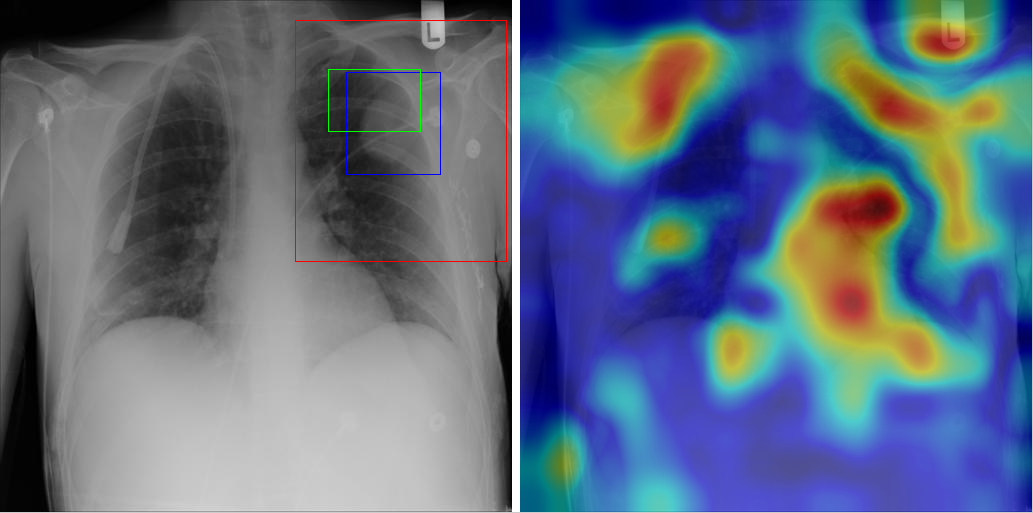

Table 8 to Table 15 illustrate localization results from each of 8 disease classes together with associated report and mined disease keywords. The heatmaps overlay on the original images are shown on the right. Correct bounding boxes (in green), false positives (in red) and the groundtruth (in blue) are plotted over the original image on the left.

In order to quantitatively demonstrate how informative those heatmaps are, a simple two-level thresholding based bounding box generator is adopted here to catch the peaks in the heatmap and later generated bounding boxes can be evaluated against the ground truth. Each heatmap will approximately results in 1-3 bounding boxes. We believe the localization accuracy and AFP (shown in Table 7) could be further optimized by adopting a more sophisticated bounding box generation method, e.g. selective search [47] or Edgebox [18]. Nevertheless, we reserve the effort to do so, since our main goal is not to compute the exact spatial location of disease patterns but just to obtain some instructive location information for future applications, e.g. automated radiological report generation. Take the case shown in Table 8 for an example. The peak at the lower part of the left lung region indicates the presence of “atelectasis”, which confer the statement of “…stable abnormal study including left basilar infilrate/atelectasis, …” presented in the impression section of the associated radiological report. By combining with other information, e.g. a lung region mask, the heatmap itself is already more informative than just the presence indication of certain disease in an image as introduced in the previous works, e.g. [42].

Radiology report Keyword Localization Result

findings include: 1. cardiomegaly (ct ratio of 17/30). 2. otherwise normal lungs and mediastinal contours. 3. no evidence of focal bone lesion. dictating Cardiomegaly [Uncaptioned image]

Table 9: A sample of chest x-ray radiology report, mined disease keywords and localization result from the “Cardiomegaly” Class. Correct bounding box (in green), false positives (in red) and the ground truth (in blue) are plotted over the original image.